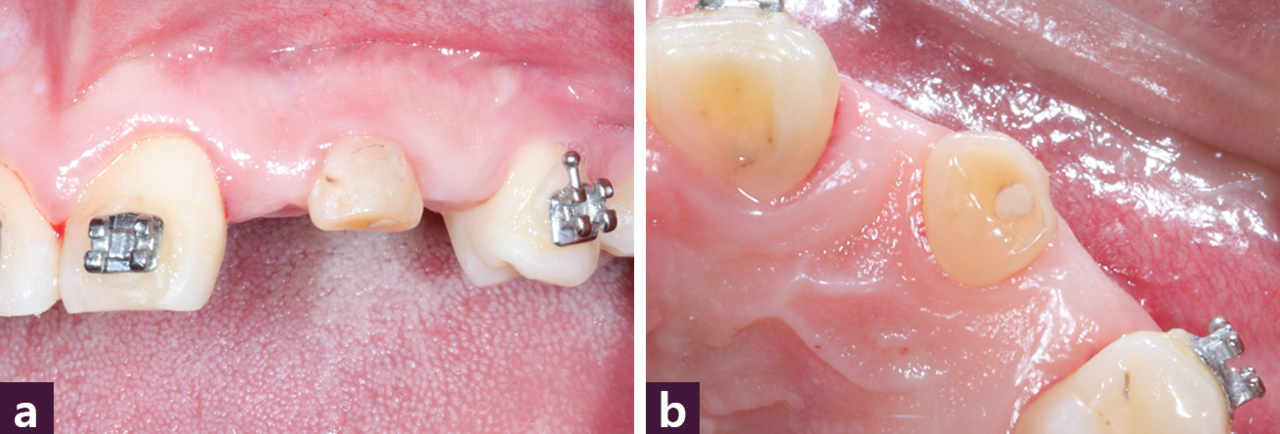

구강 내 사진으로 #22, 23의 중간부위에 #63이 남아 있으며 순측의 concavity를 확인할 수 있다 [그림 13].

임플란트가 위치될 이상적인 부위에 Magic Guide Pin을 꽂고 CBCT를 촬영하여 치 조골의 폭, 길이, 골질 등을 평가한 후 Magic Guide Pin을 따라서 drilling을 시행한다 [그림 14].